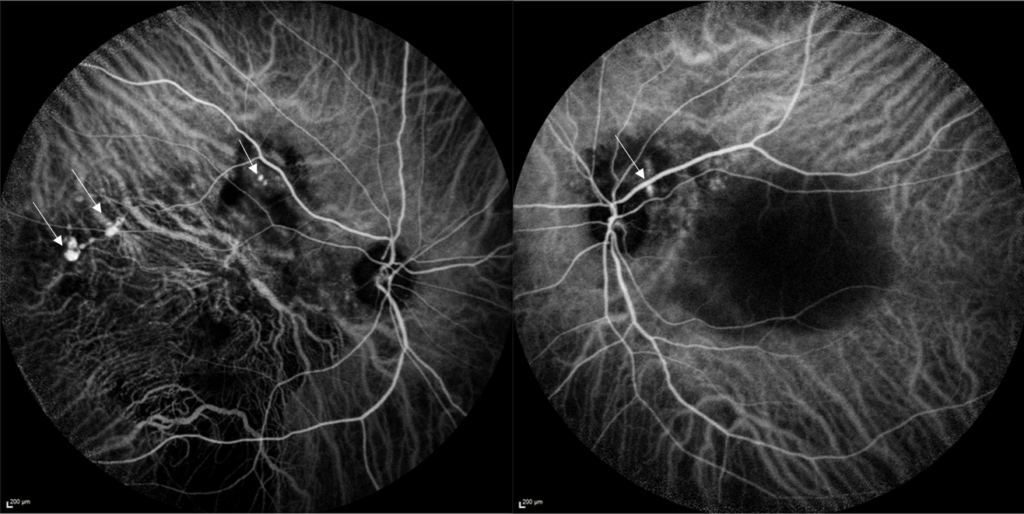

L’OCT* (Tomographie par Cohérence Optique) permet de visualiser en coupe les différentes couches de la rétine, la présence de liquide intra ou sous rétinien. L’angiographie à la fluorescéine* et au vert d’indocyanine* permet de localiser les polypes, les différents points de fuite, et la présence de néovaisseaux anormaux.

Angiographie en ICG montrant la présence de polypes sur les deux yeux (flèches)